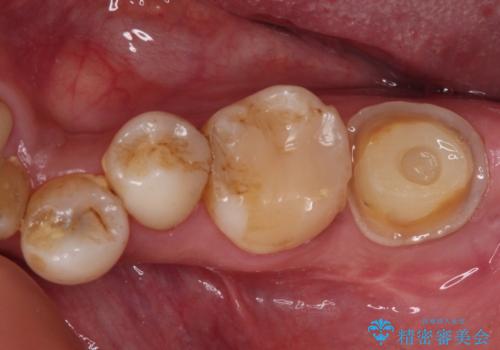

セラミックは無理と言われた奥歯 フルジルコニアクラウンによる補綴治療